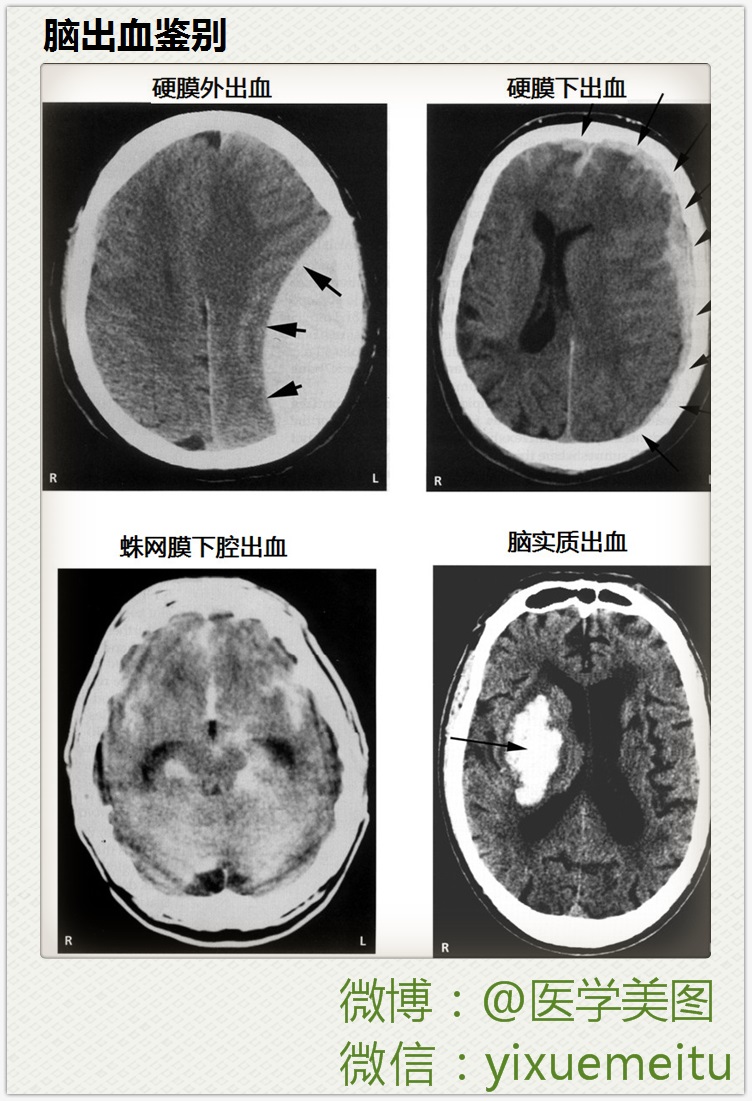

2015医学美图联播 l 神经科(33图)